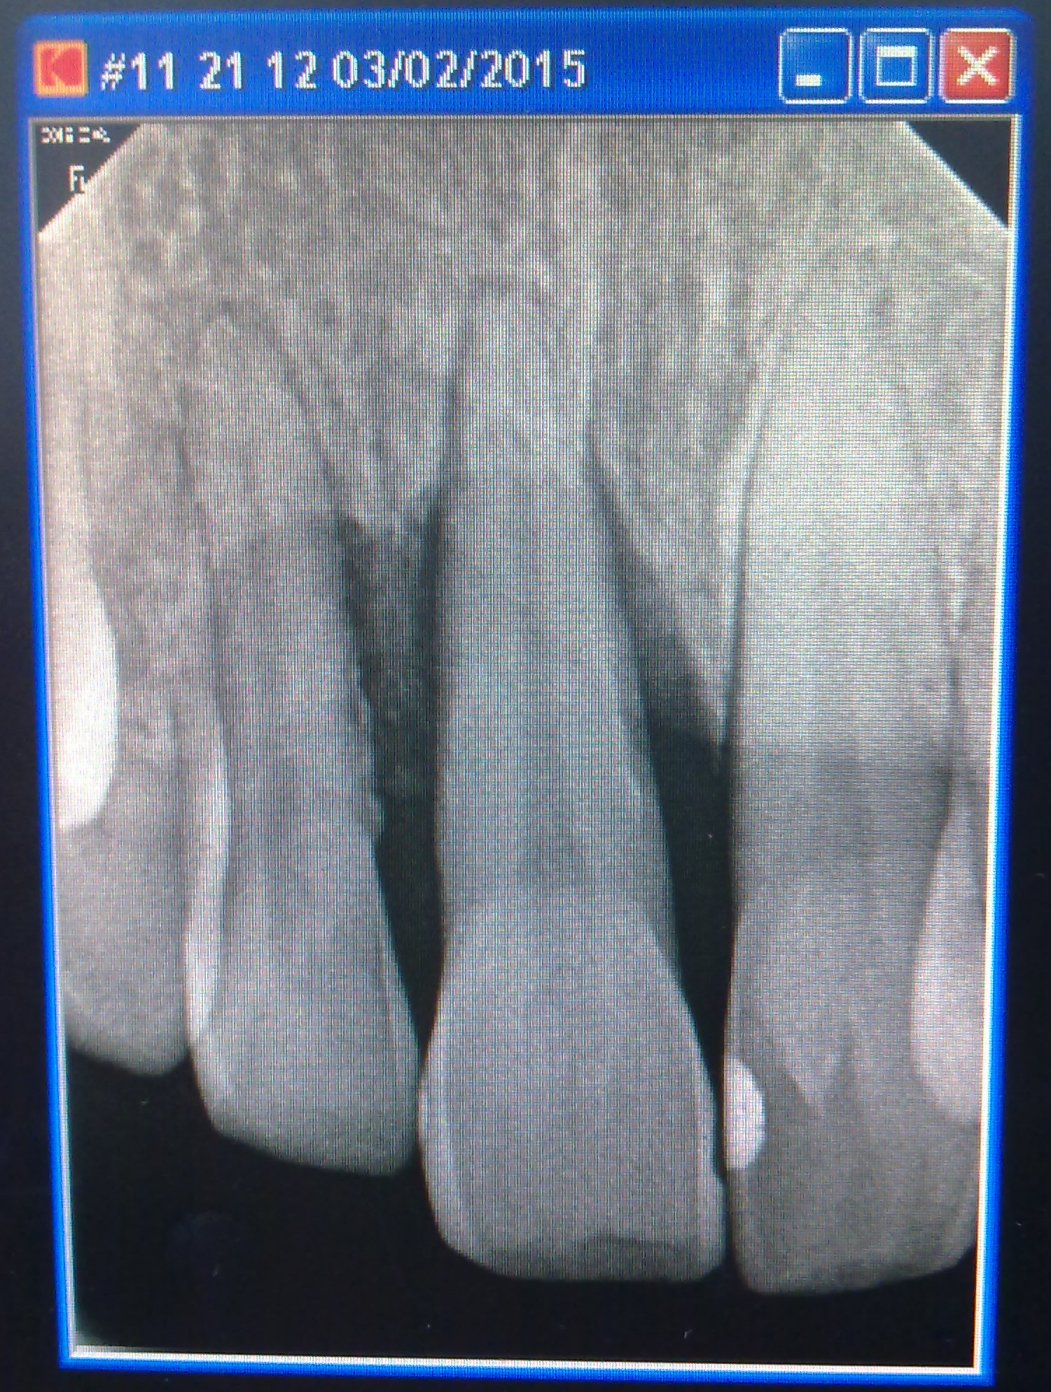

И ещё у меня на рентгене зуба вокруг корня затемнения. Врач сказал, что туда попала инфекция и надо лечить, пять дней уколы колоть. Действительно, можно вылечить этот зуб? В прошлый раз после таких затемнений на другом зубе в конце-концов пришлось удалять зуб.

Снимок покажите. Уколов никаких даже и не вздумайте делать. Эти уколы - чушь, и можете смело плюнуть в любого, кто заявит обратное.

И ещё у меня на рентгене зуба вокруг корня затемнения. Врач сказал, что туда попала инфекция и надо лечить,

Затемнение означает лизис костной ткани. Кушать он у вас не просит только потому, что он - воспалительный процесс - тупо жрёт кость. Иметь хронические очаги воспаления в организме - не есть хорошо.

Если он действительно так безнадежен, то он уже должен болтаться в челюсти, как сами знаете что. Если он ещё крепко сидит в кости, то скорее всего там не все так безнадежно. А так можно дождаться, что пока он начнет шататься. соседние зубы тоже станут шевелиться ему в такт. Но повторюсь, зуб этот ваш и только вам решать нужен он вам или нет. :) Мне просто кажется логичным не дожидаться острой боли, а тихо и спокойно планово удалить этот зуб, если он уже нежилец. Смысл дарить микробам инкубатор?

Нуждаюсь в вашем совете. У меня с прошлой недели после сильной простуды воспалились дёсна, особенно верхний правый резец (заячий зуб) и тот что возле него. Сходил к врачу в клинику что возле 16ой больницы на Чиланзаре. Врач сделала рентген и выявила пародонтоз. Мне 37 лет. Остальные зубы вроде нормальные. Есть конечно повреждения костной ткани, но зубы не шатаются. Врач предлагает удалить нерв в этих двух зубах, с аргументацией, что если удалить нерв, то кровоснабжение зуба прекратится и этот высвободившийся кровоток будет лучше снабжать десну. Я покопался в нете, но об этом не смог найти ничего. Т.е. что при пародонтозе (а может у меня всё таки пародонтит?) помогает депульпация. Врач никакой гарантии на сохранение зуба не даёт!

Снимок можете показать?

Прошу прощения, что так долго отвечал... никак не мог прикрепить требуемый снимок к сообщению. как то замысловато сделано здесь.

Пожалуйста, подскажите что и как с моими зубами и куда можно обратиться? Правильно ли назначили лечение с удалением нерва? И что ещё можно сделать чтобы спасти зубы?

Добавлю ещё инфу (может даже по снимку видно): эти два зуба шатаются больше наружу, внутрь ротовой полости они не шатаются. В стороны совсем чуть-чуть.